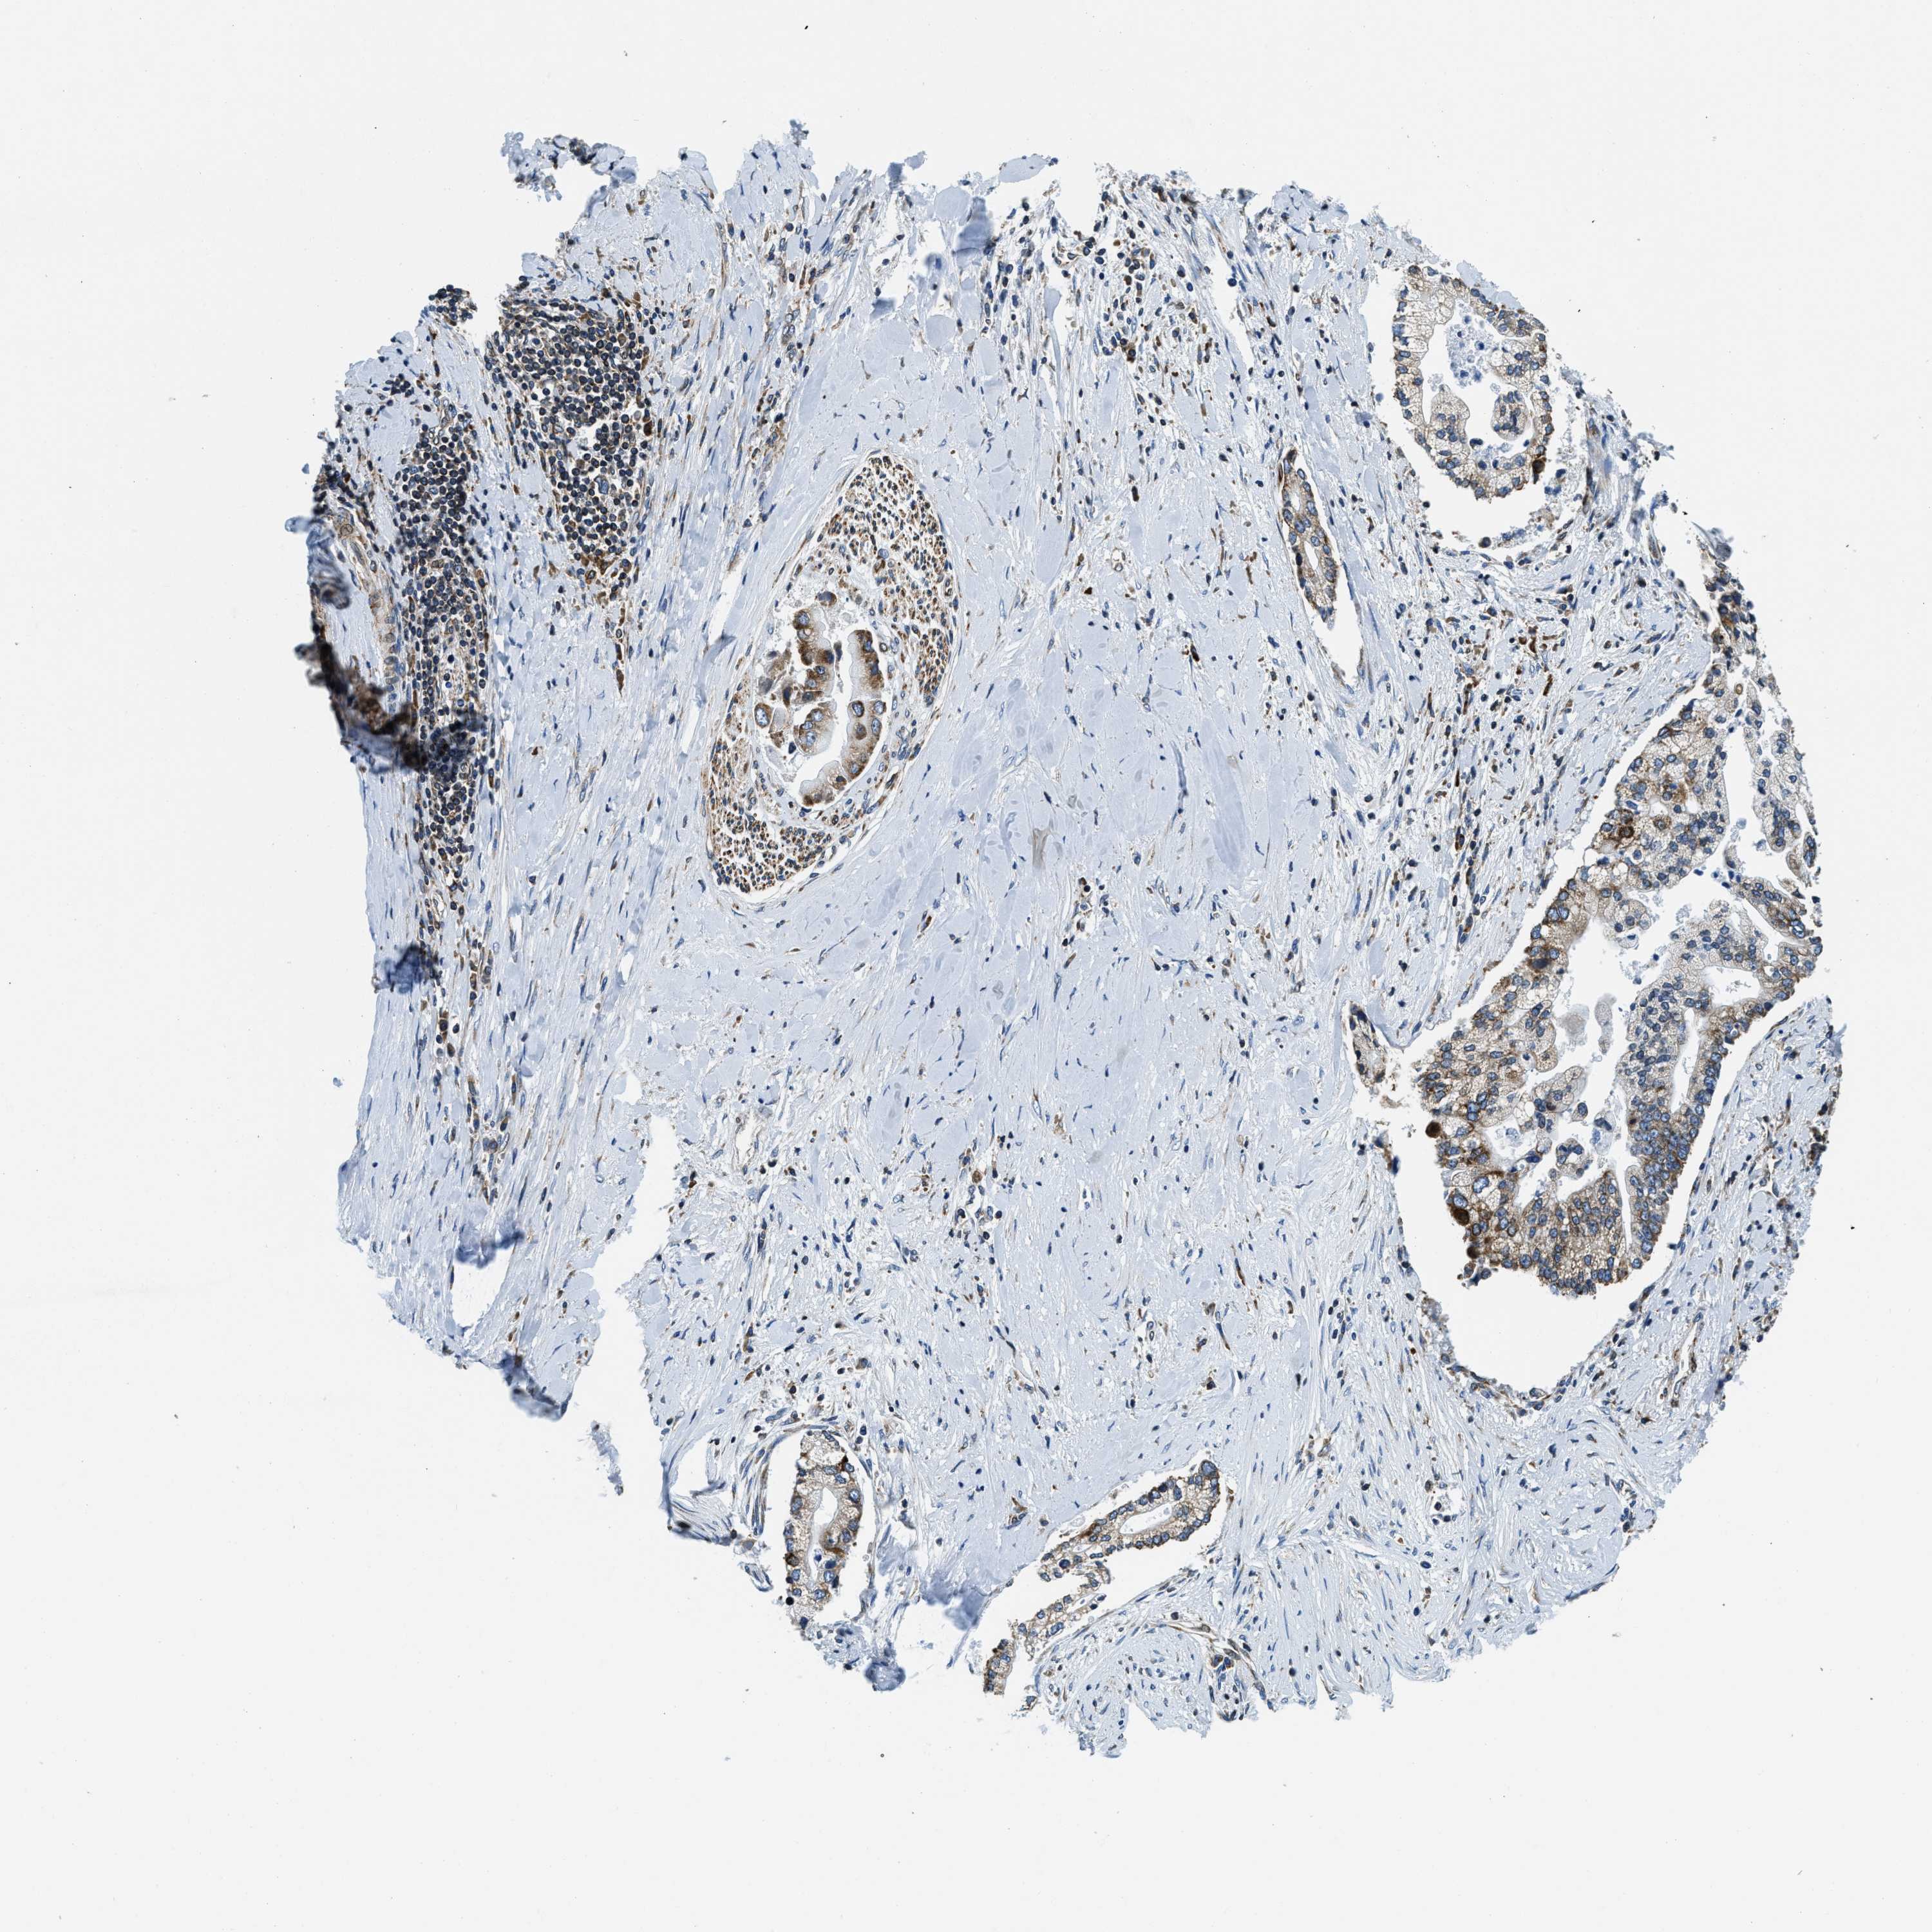

LIVER CANCER - Protein expressioni

A mouse-over function shows sample information and annotation data. Click on an image to view it in a full screen mode. Samples can be filtered based on level of antibody staining by selecting one or several of the following categories: high, medium, low and not detected. The assay and annotation is described here.

Note that samples used for immunohistochemistry by the Human Protein Atlas do not correspond to samples in the TCGA dataset.

Antibody stainingi

Antibody staining in the annotated cell types in the current human tissue is reported as not detected, low, medium, or high, based on conventional immunohistochemistry profiling in selected tissues. This score is based on the combination of the staining intensity and fraction of stained cells.

Each image is clickable and will lead to virtual microscopy that enables deeper exploration of all samples and also displays staining intensity scores, fraction scores and subcellular localization as well as patient and tissue information for each sample.

Antibody HPA019698

Staining

High

Medium

Low

Not detected

Intensity

Strong

Moderate

Weak

Negative

Quantity

>75%

75%-25%

<25%

None

Location

Nuclear

Cytoplasmic/membranous

Cytoplasmic/membranous,nuclear

Cholangiocarcinoma

Carcinoma, Hepatocellular, NOS